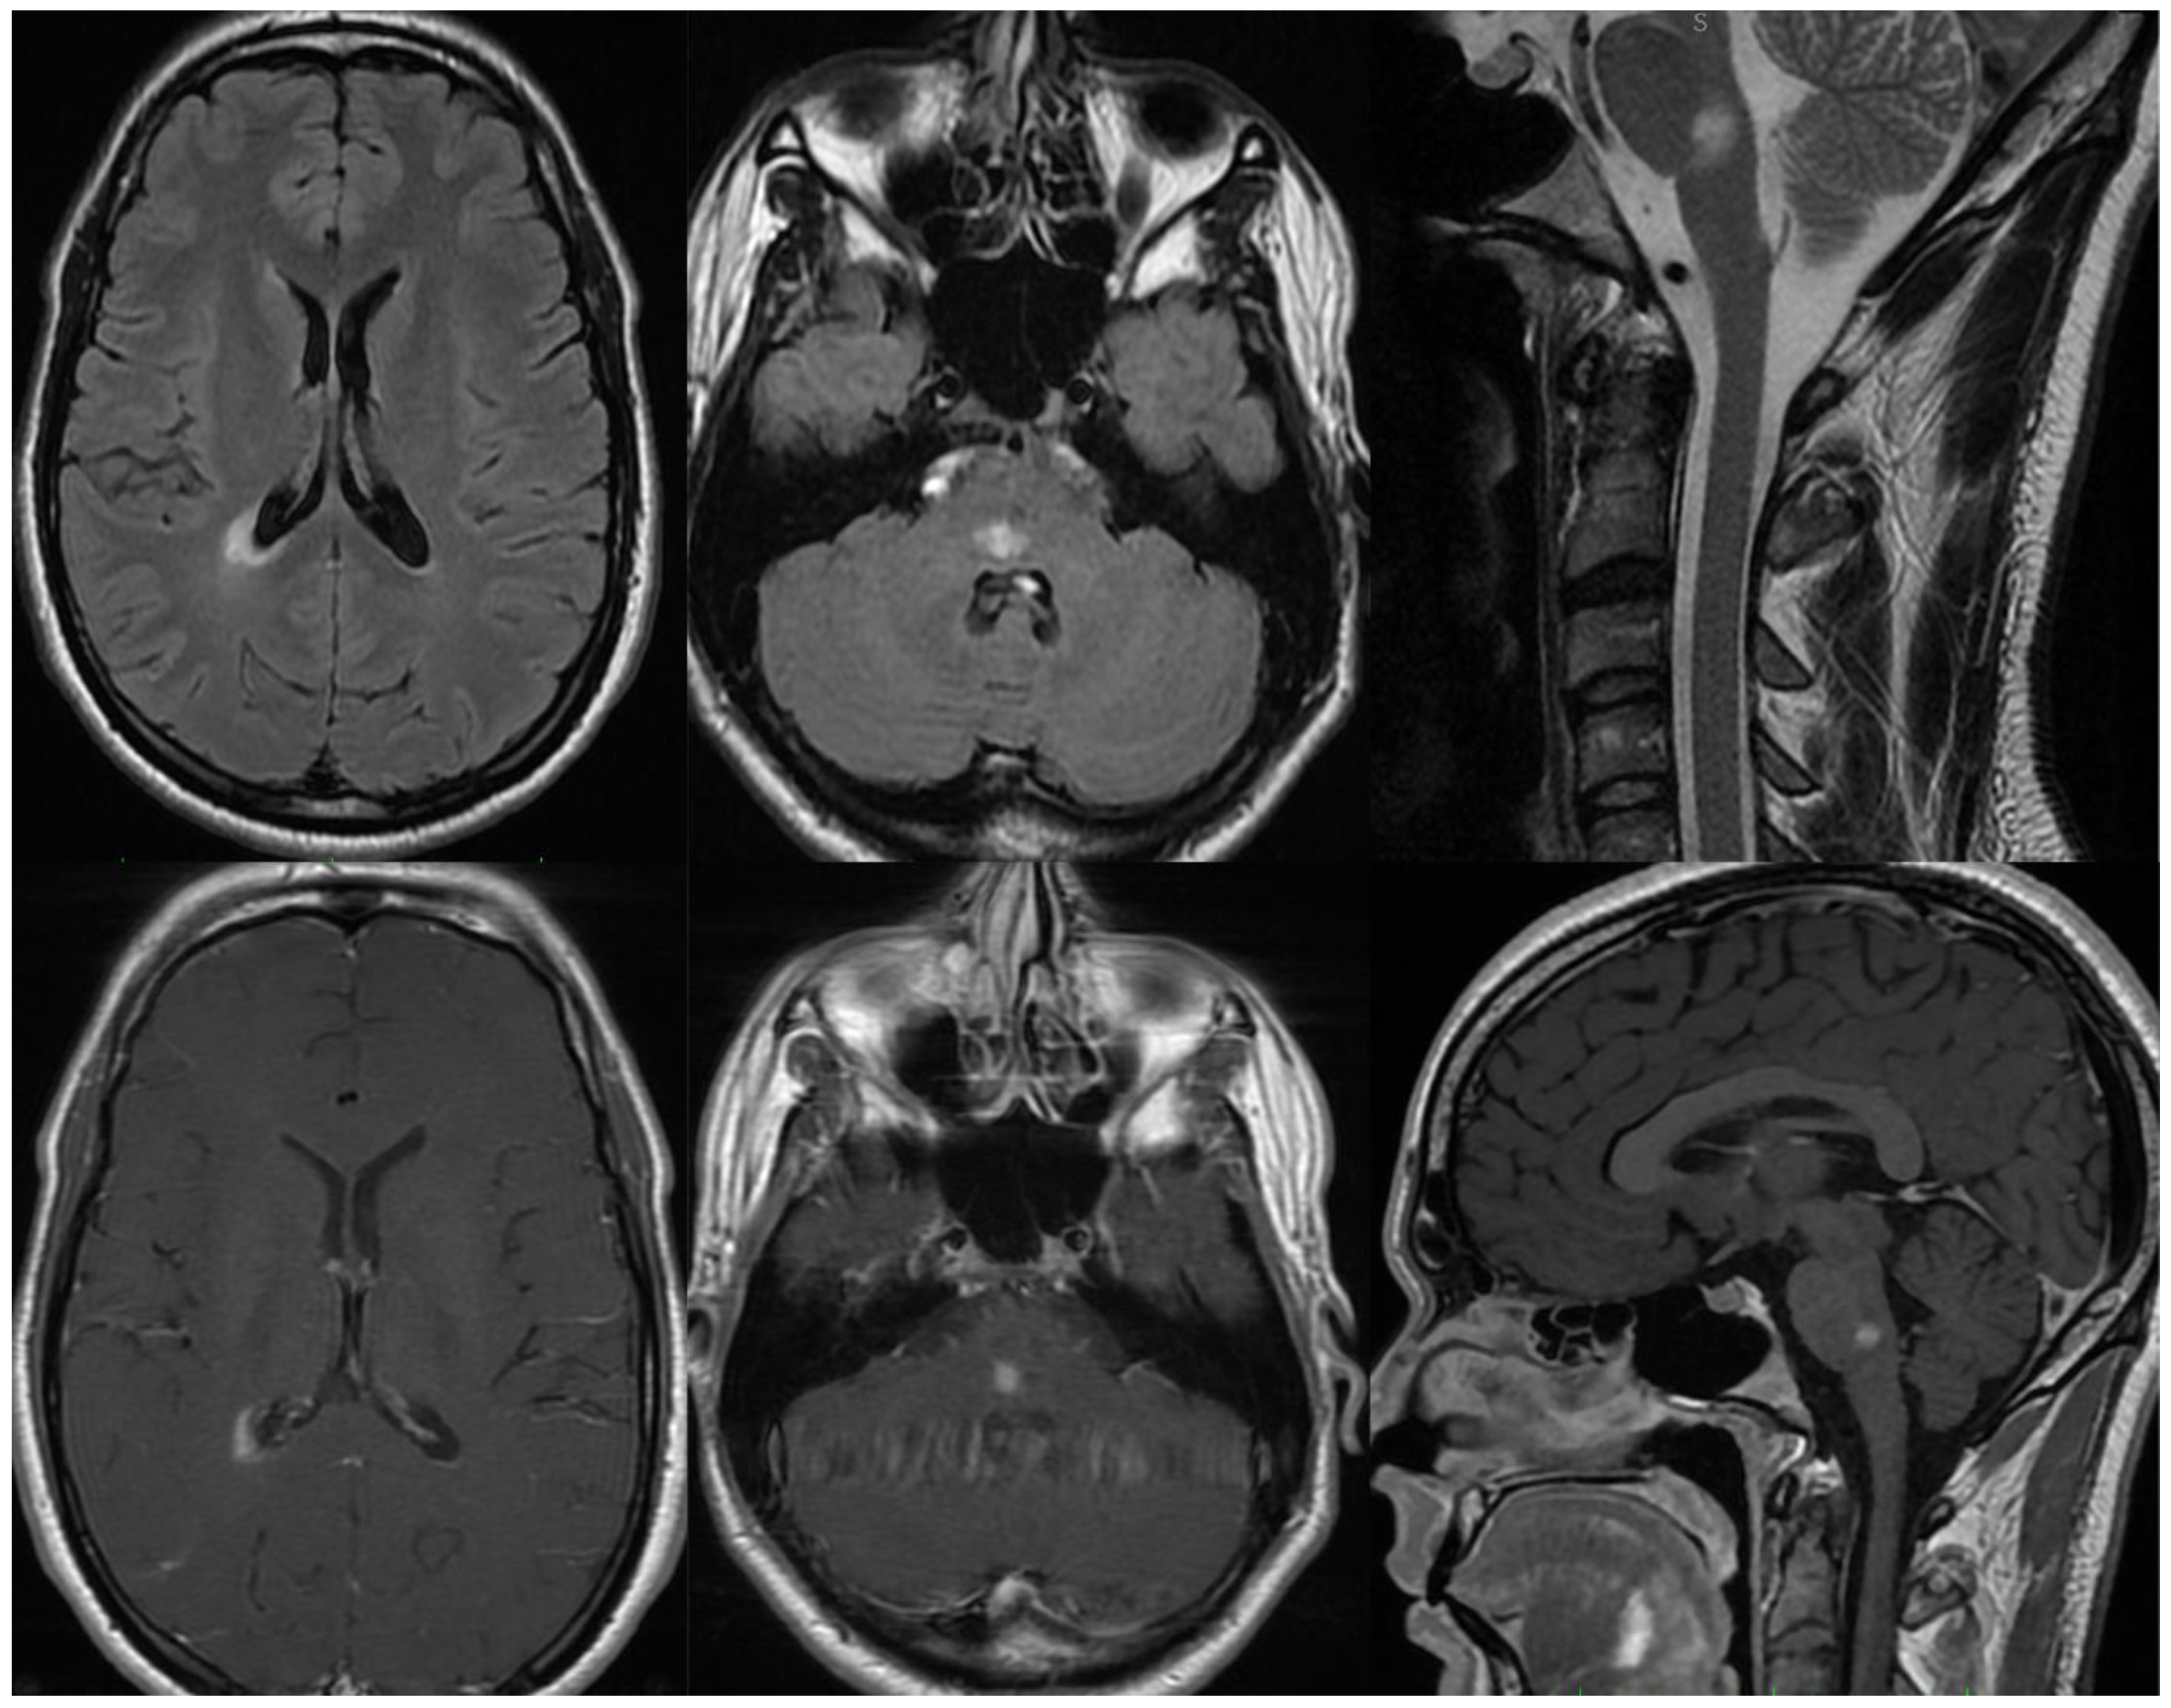

3.1.1. Patient 1

3.1.2. Patient 2

3.1.3. Patient 3